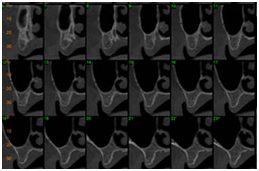

As imagens visualizadas abaixo representam os cortes tomográficos transversais oblíquos efetuados na imagem guia. Nesse caso foram realizados cortes tomográficos com espessura de 1mm e distância entre cada corte também de 1mm. Essa seleção é feita pelo operador do tomógrafo e permite escolher a distância e a espessura dos cortes que podem ser de 1 ou 2mm.

TC cortes transversais obliquos TC cortes transversais obliquos

TC cortes transversais obliquos